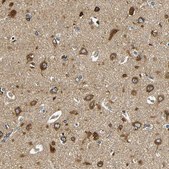

Vesicle-associated membrane protein-associated protein B/C (VAPB) belongs to the VAP family. It contains three structural domains: the major sperm protein (MSP) domain, an amphipathic helical structure and a carboxy-terminal domain that acts as a membrane anchor. VAPB is localized in intracellular membranes of the endoplasmic reticulum and Golgi apparatus. The gene encoding this protein is located on chromosome 20q13.3.

The Human Protein Atlas project can be subdivided into three efforts: Human Tissue Atlas, Cancer Atlas, and Human Cell Atlas. The antibodies that have been generated in support of the Tissue and Cancer Atlas projects have been tested by immunohistochemistry against hundreds of normal and disease tissues and through the recent efforts of the Human Cell Atlas project, many have been characterized by immunofluorescence to map the human proteome not only at the tissue level but now at the subcellular level. These images and the collection of this vast data set can be viewed on the Human Protein Atlas (HPA) site by clicking on the Image Gallery link. We also provide Prestige Antibodies® protocols and other useful information.

Biochem/physiol Actions

• IHC tissue array of 44 normal human tissues and 20 of the most common cancer type tissues.